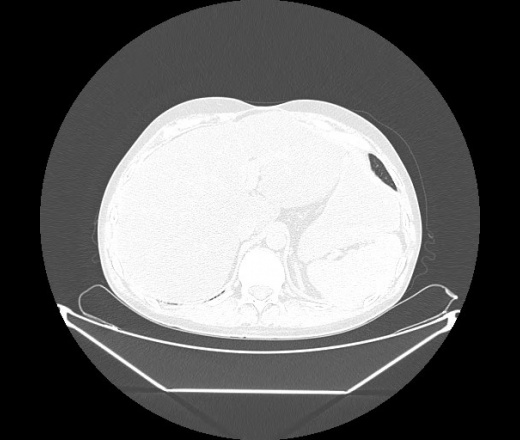

М. 1984 г.р.  Лихорадка 39, кашель , одышка.. и надоевший всем вопрос- "типично ли для ковид?" ( в настоящее время на него обязательно нужно дать ответ в своем протоколе)

На мой взгляд нетипично для ковид: много центрально-расположенных поражений, лобарное поражение нижней доли слева. 50/50

Не типичая картина для ковид.

КТ-признаки двусторонней бактериальной пневмонии.

Все верно, здесь абсолютно нетипичная картина, несмотря на матовое стекло с ретикулярными изменениями, но почему-то  посчитали иначе. Кстати,  "малыша" не заметили)?